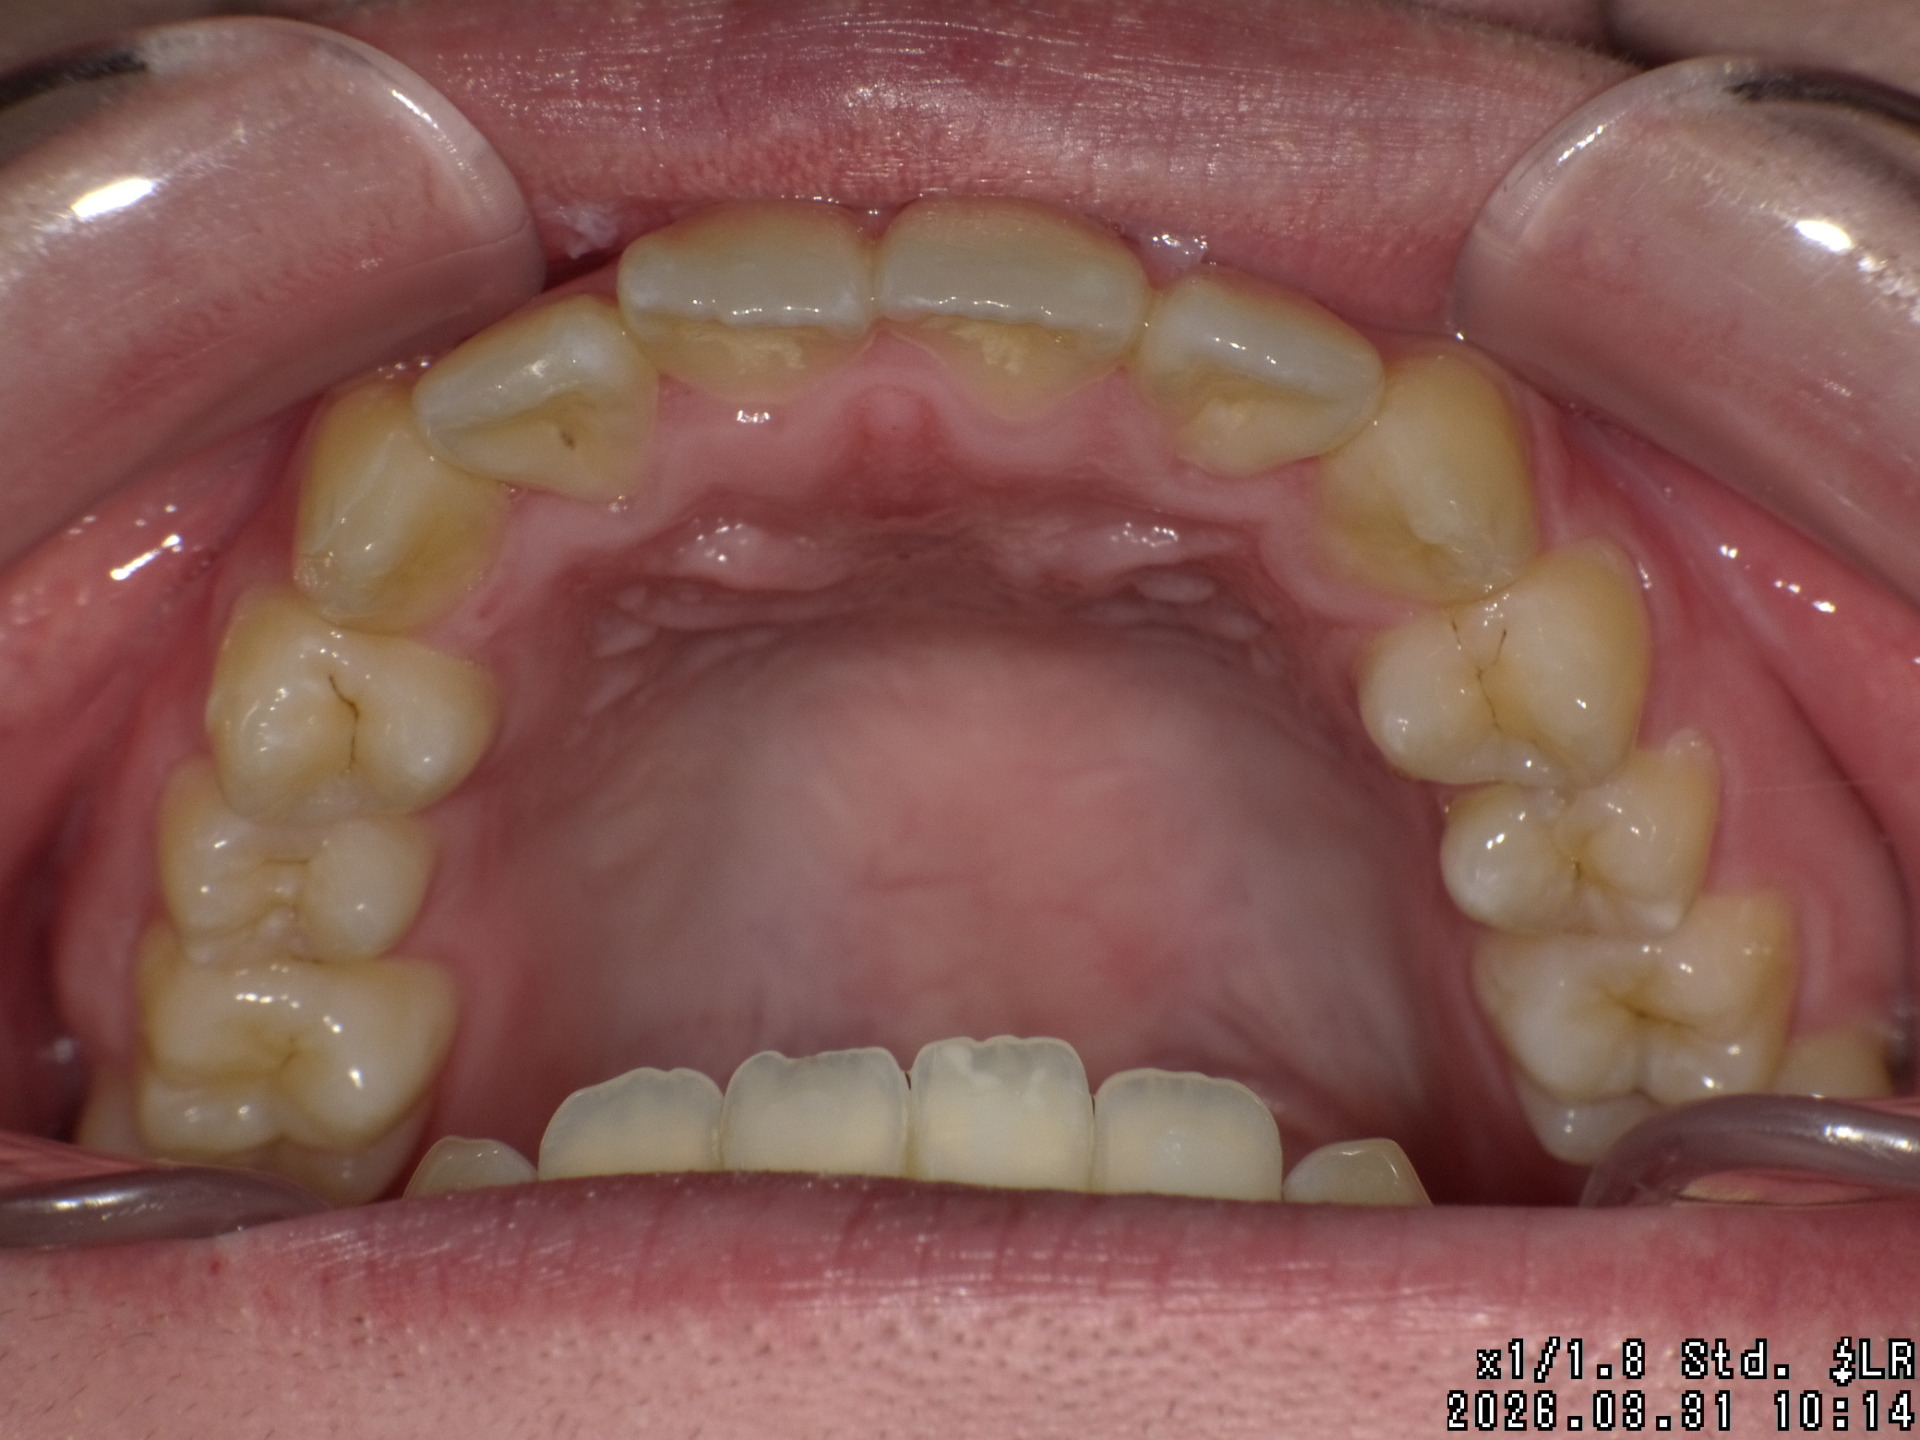

Before

| 症状 | 右上八重歯 上顎正中の著しいずれ |